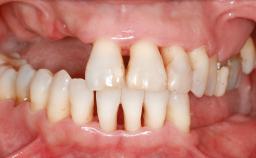

Iliac and Calvarial Bone Blocks for Onlay Grafting of a Severely Resorbed Edentulous Maxilla

A 45-year-old woman with a completely edentulous maxilla was referred to evaluate the possibility of rehabilitation with an implant-supported prosthesis. This patient was healthy and a non-smoker. She had been wearing a maxillary complete denture opposing a natural mandibular dentition since her twenties. This situation had resulted in progressive resorption of the alveolar ridge, repeatedly creating a need for relining the denture. Twenty years later, despite multiple adaptations and the use of “glues” the denture was unstable and causing the patient psychological and functional discomfort.

Bone Augmentation Horizontal|Sinus Floor Elevation|Staged|Vertical

Augmentation Materials Autogenous chips|Autogenous block(s)